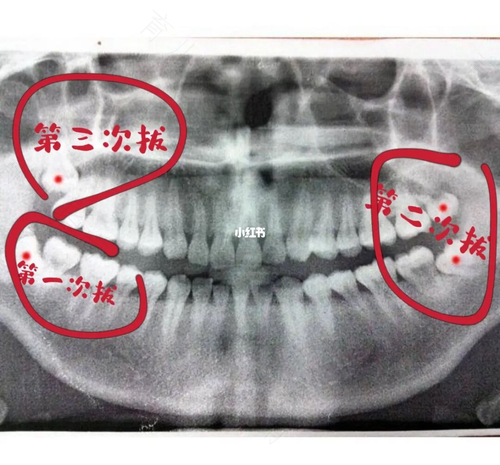

人们一般在16~25周岁期间,会进行智齿的发育和生长,然而也不是长出来的智齿全都要拔掉,因为有些人的口腔条件还是比较好的,智齿长出来是不会产生疼痛,所以也就不需要拔出。而有些人的智齿长出来之后就会忍受很大的痛苦,这样的情况是需要拔除的,那拔智齿第几天是最重的时候?